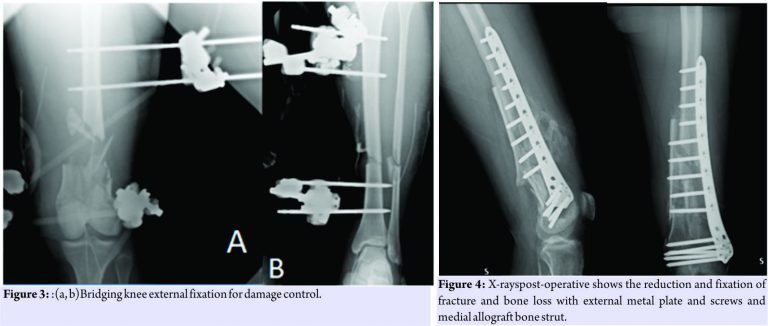

The patient was treated in emergency with a bridge femorotibial external fixator after extensive cleaning and debridement of open fractures(Fig.3a and b). After stabilization, the wounds were covered with iodine-impregnated incision drape (Ioban). During the damage control’s operations, a fragment of 8 cm × 3 cm × 4cm of bone substance corticospongiosa was found in the left sock. The fragment was immersed in a solution of cefuroxime, gentamicin, and metronidazole and maintained at a temperature of −3°C until 2h before the intervention because it was irradiated with a dose of 25kGy. The 4days, we removed the antibiotated chains and the Ioban cover which were replaced with vacuum therapy. The patient never had fever over 38°Cduring his 10 days in intensive care and in the ward. The delayed risk of tibial consolidation was equal to 8 of 10 according to A.R.R.C.O. As regards the femur, the risk of non-union of the fracture of the femur of 51 points according to the non-union scoring system(N.U.S.S)

The patient was not treated surgically for the fissure of the spleen, and the resolution of the neurological picture took place after 6 days. The patient was submitted to a specific antibiotic therapy according to the protocol for the open fractures and was monitored with clinical and laboratory examinations. The 21stday post-trauma, without any clinical or laboratory signs, the patient was operated on with a less invasive stabilization system plate and screws, cortical and cancellous bone grafting allogeneic bank, and autologous stem cells taken from the iliac crest, PRP rich in leukocytes and replanting of native bone. The surgical access chosen was the lateral subvastus to preserve the perforating arteries(Fig.4). The patient was monitored with 15 days clinical follow-up, laboratory, and radiological at 1 month, 2 months, 3 months, 6 months, 12 months, 18 months, 24 months, 36 months, and 48 months. The indices used to evaluate the outcomes of this intervention were the knee injury and osteoarthritis outcome score (KOOS), the related union scorefemur (R.U.S.F.) for the femoral bone healing, and the score radiographic union score for tibial fractures (R.U.S.T.). For bone consolidation of shank, the short form 12 health survey (SF-12) for the quality of life, and the number of complications and re-operations. The patient in the immediate post-operative made active and passive mobilization of the knee until the 3rdmonth, reaching a flexion of 90°. The patient was subjected to the intervention of removal of the external fixator and intramedullary nailing of the tibia 3 months after the first surgery(Fig. 5)